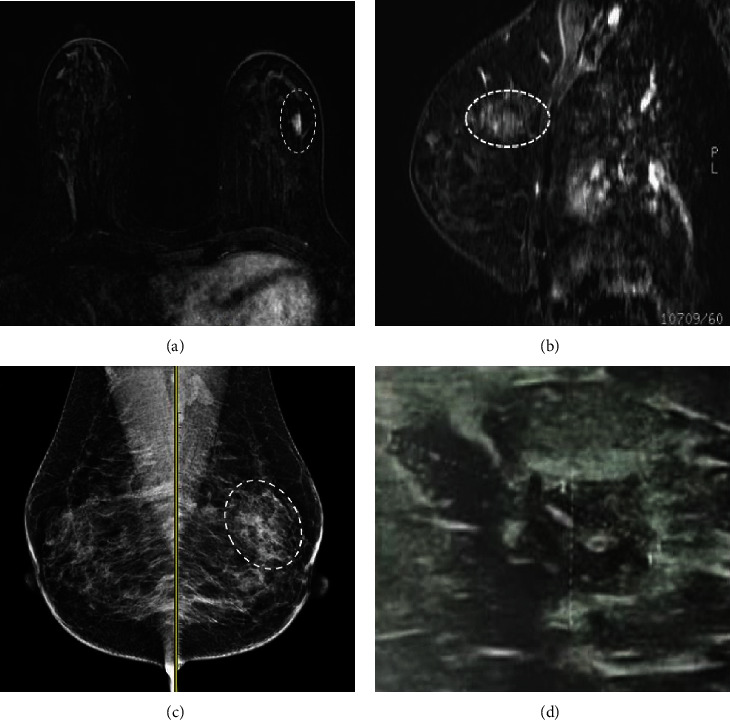

Dynamic contrast-enhanced magnetic resonance imaging (DCE-MRI) is a highly sensitive breast imaging modality in detecting breast carcinoma. Nonmass enhancement (NME) is uniquely seen on MRI of the breast. The correlation between NME features and pathologic results has not been extensively explored. Our goal was to evaluate the characteristics of probably benign and suspicious NME lesions in MRI and determine which features are more associated with malignancy. We performed a retrospective research after approval by the hospital ethics committee on women who underwent breast MRI from March 2017 to March 2020 and identified 63 lesions of all 400 NME that were categorized as probably benign or suspicious according to the BI-RADS classification (version 2013). MRI features of NME findings including the location, size, distribution and enhancement pattern, kinetic curve, diffusion restriction, and also pathology result or 6-12-month follow-up MRI were evaluated and analyzed in each group (probably benign or suspicious NME). Vacuum-guided biopsies (VAB) were performed under mammographic or sonographic guidance and confirmed with MRI by visualization of the inserted clips. Segmental distribution and clustered ring internal enhancement were significantly associated with malignancy (p value<0.05), while linear distribution or homogeneous enhancement patterns were associated with benignity (p value <0.05). Additionally, the plateau and washout types in the dynamic curve were only seen in malignant lesions (p value <0.05). The presence of DWI restriction in NME lesions was also found to be a statistically important factor. Understanding the imaging findings of malignant NME is helpful to determine when biopsy is indicated. The correlation between NME features and pathologic results is critical in making appropriate management.

Abstract Image